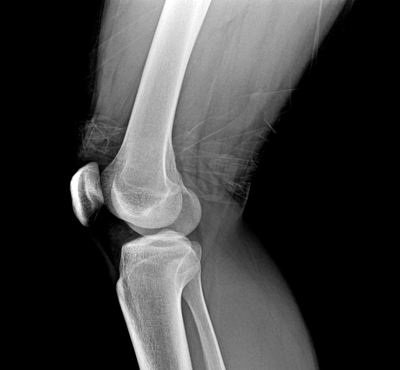

The Meniscus is a crescent-shaped fibrocartilaginous structure, located on the medial and lateral side of the knee joint. The meniscus protects the knee joint by alleviating the pressure on the knee and supporting the correct functioning of the knee. Meniscus damage in younger patients is typically caused by sports injuries, while meniscus damage in elderly patients is more often observed as a degenerative disorder. It is more common in women than men, and considered to be caused by pressure and stress accumulated from the individual's daily routines.

If the meniscus damage is not treated on time, it often develops into a more serious disease such as degenerative arthritis. In clinical trials of TG-C, evidence of the improvement of meniscus injury was observed, which suggests the potential for meniscus treatment by TG-C.